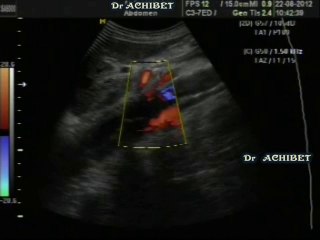

Dissection et bases anatomiques de l'aorte thoracique